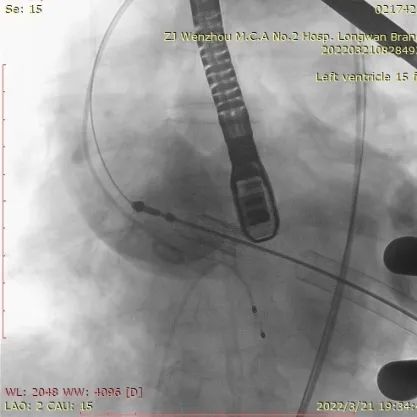

4.患者术中造影角度LAO:1°,CAU:15°。

术中DSA参考投照角度:LAO 1°,Caudal 15°

经股静脉置入临时起搏器,并经股动脉植入6F猪尾管。行第五肋间小切口并在心尖部缝制荷包。穿刺心尖后进泥鳅导丝过主动脉瓣经过主动脉弓到达降主动脉膈肌水平。单弯管交换硬导丝后,用16F扩张鞘预扩心尖穿刺处,后将 J-Valve瓣膜(27mm)装入输送器并经心尖穿刺处推送至主动脉根部,释放定位件,并微调角度使其入窦,后完全释放瓣膜,撤出输送器。通过DSA和TEE观察人工瓣膜膨胀后金属支架的形态、位置,有无瓣周漏。撤出导丝,收紧心尖处荷包线并打结,后鱼精蛋白中和肝素,彻底止血,逐层关胸,封皮,拔出股动脉鞘并在股动脉穿刺处压迫止血。手术过程顺利,患者生命体征平稳。

释放定位件

瓣膜入座

瓣膜自膨